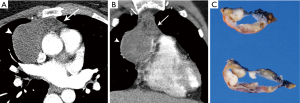

Cystic thymomas (Figure 2) and benign thymic cysts may mimic one another, with MRI very useful for differentiating these entities. MRI may identify fibrous internal septae, soft tissue mural nodularity, and enhancement, as well as characterize fluid as simple, proteinaceous, or hemorrhagic. Any foci of hemorrhage would appear T1 hyperintense. Soft tissue components are hypo to iso-intense on T1-weighted images, and hyperintense on T2-weighted sequencing. In addition to MRI’s superiority to CT in discerning soft tissue components and fluid characterization, it may also be helpful in distinguishing local invasion. PET/CT does not have a large role in terms of diagnostic specificity.

Certain morphologic and imaging features can indicate advanced disease (Figure 3). Key findings to identify include mediastinal pleural invasion or pericardial extension and invasion, loss of fat planes between mediastinal vasculature and viscera, and nodal or metastatic lesions. Pleural, pericardial or distant metastases are exceedingly rare in types A and AB thymoma. Local recurrence/spread is estimated to occur in less than 5% of type B1, 11% of type B2, and 18% of type B3 thymomas; distant metastases occur in approximately 3% with types B2 and B3 thymomas (3).

On imaging, thymic carcinoma is more likely to be poorly or irregularly marginated and more likely to have internal heterogeneity due to calcification or cystic/necrotic change (Figure 5A). Thymic carcinomas are often associated with pericardial or pulmonary parenchymal invasion (40%), pleural invasion (30%), and vascular invasion (20%) into the superior vena cava or brachiocephalic veins (3). Additionally, a higher proportion, approximately 19–50%, present with distant metastases, most often to bone, liver, lung, and adrenal gland, at time of diagnosis in comparison to thymoma (3). Pericardial effusion, pleural effusion, or enlarged lymph nodes are also more likely with thymic carcinoma than thymoma.

Thymoma and thymic carcinoma have different MR characteristics. Thymic carcinomas are hyperintense on both T1 and T2 weighted images, distinct from the T1 hypointensity of thymomas, and there may be signal heterogeneity due to calcification, necrosis and/or hemorrhage. Soft tissue components will enhance on post-contrast images, and invasion into adjacent structures may be more clearly delineated. MR can identify distant metastatic disease in the pleura, lymph node stations, and bones included in the area imaged.

The histological diagnosis of thymic carcinoma is characterized by the clearly malignant features of the epithelial cells and the absence of TdT positive lymphocytes (Figure 5B), in contrast to thymoma.